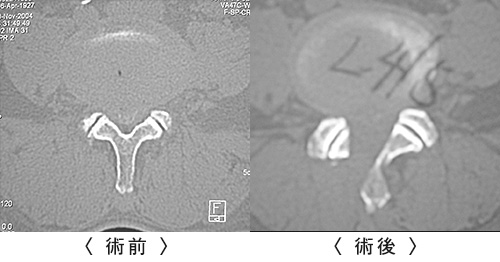

腰椎除圧・固定術(ようついじょあつ・こていじゅつ)

- 第5腰椎分離すべり症

- 神経(硬膜管・神経根)の圧迫を取り除いた後に腰椎の不安定性が生じる場合があり、術後の安定性を得るために腰椎を固定する手術です。

当科では、脊椎インストゥルメンテーション(脊椎内固定具)を使用した脊柱再建・固定手術を行っております。脊椎インストゥルメンテーションを併用した脊柱固定手術を行うことで、より確実に手術後の固定性が獲得でき、安定した臨床成績が得られます。